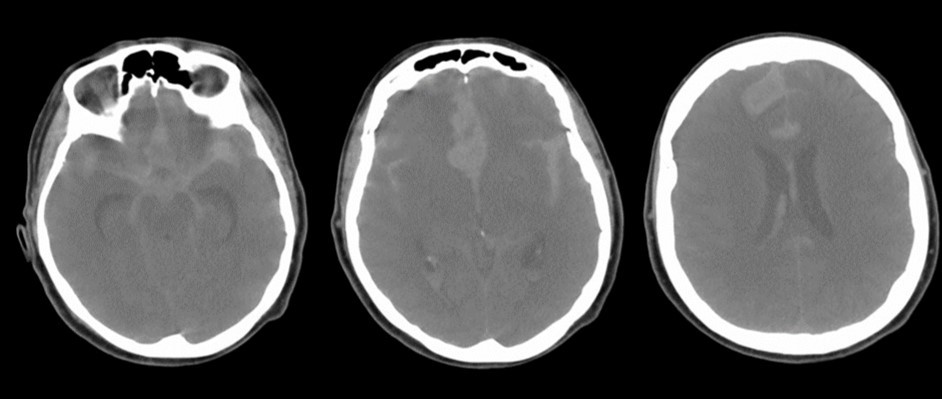

A 65 years-old woman with no relevant medical history was carried to the emergency department of another institution for the sudden onset of headache and vomiting, followed by loss of consciousness. She underwent a cerebral CT scan, that showed diffuse SAH in the basal cisterns and anterior interemispheric fissure (Figure 1). The CT angiogram displayed a single aneurysm of the anterior communicating artery, that local radiologists considered unfavorable for endovascular treatment. The patient was therefore surgically managed, with left pterional craniotomy for aneurysm clipping and right external ventricular drain (EVD) positioning. In the following days the woman reacquired alertness; the EVD was removed without need of permanent shunting and she was transferred to rehabilitation four weeks after the operation in quite good conditions.

Figure 1.Non-contrast axial CT scan showing thick subarachnoid hemorrhage in the basal cisterns and in the frontal interemispheric space

The clinical and radiological features of these two diseases are perfectly known to neurosurgeons; anyhow our case shows that trouble rises when they do occur simultaneously. The patient we described had initially acute signs due to SAH and later signs that were incorrectly interpreted as SAH-related. The tumor was almost invisible -because of its likely small volume and thick SAH- in the first CT performed (Figure 1). Analyzing the early follow-up CT (Figure 2) anyway things do not seem so clear. In the frontal region remained too much fogging close to the midline; the asymmetric distribution of such alteration should had point out a problem, but everybody kept thinking to a “simple” post-hemorrhagic condition, due to ventricular enlargement and focal ischemia. The initial mental impairment of that period was equally attributed to a normal SAH result with moderate hydrocephalus. The proper diagnosis of glioma happened late, and the patient was at that point unable to have significant benefits from surgery.